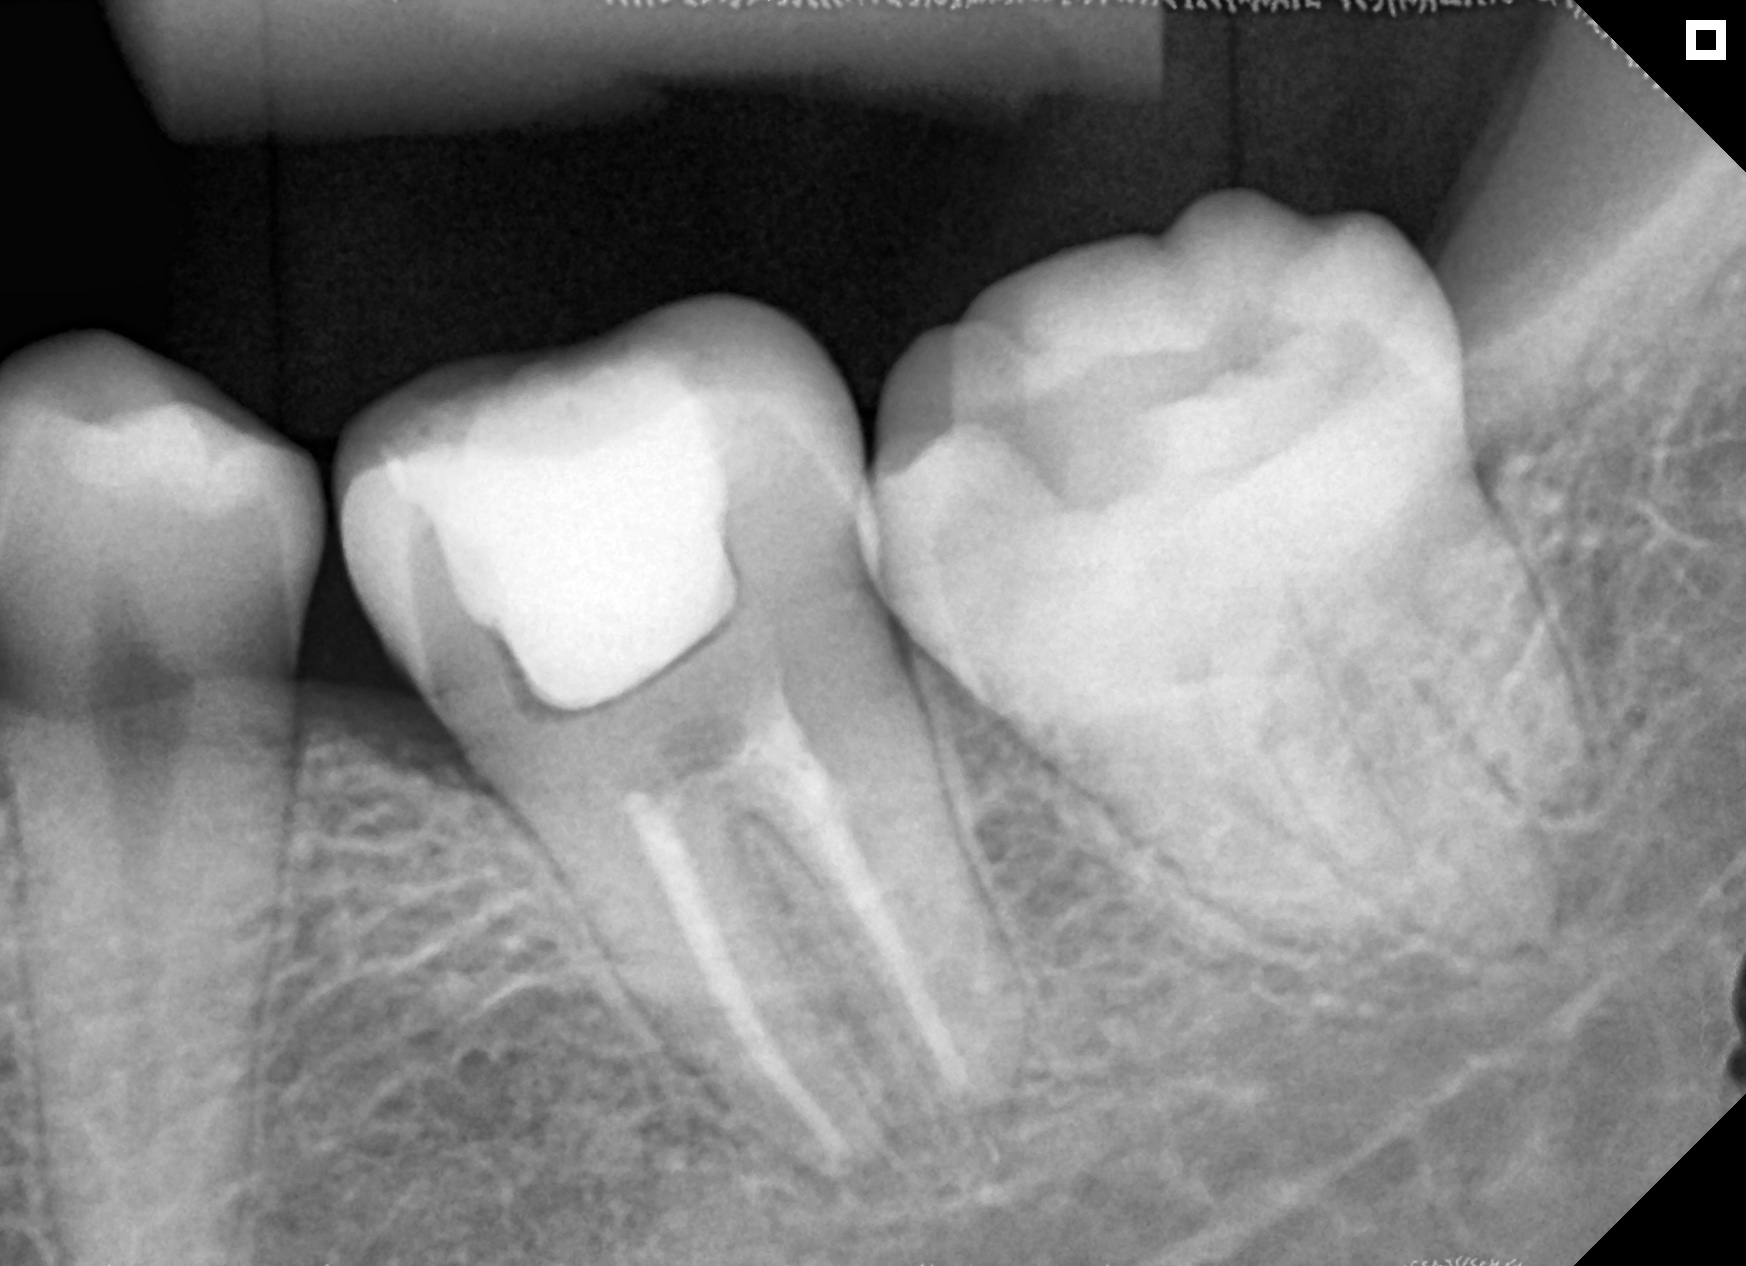

Microscópio e Raio-X Portátil. Equipamentos de última geração e técnicas avançadas para resultados excepcionais e seguros.

Resultados reais com tratamentos personalizados.

Antes

Depois